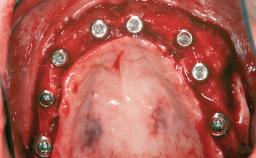

Bone Augmentation Horizontal|Staged

Augmentation Materials Autogenous chips|Autogenous block(s)|Xenogenous|Membrane